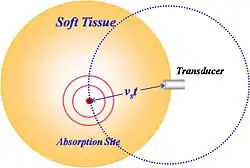

The typical acoustic detector is an ultrasound transducer, which is commonly made of a piezo-electric material that converts detected pressure to an electrical signal. Thermoacoustic waves are induced within the anatomy wherever absorption takes place, and the strength of these thermoacoustic waves is proportional to the energy absorbed within the tissue. Some of these waves propagate through the anatomy over some time interval (time-of-flight) before being detected by one or more of the acoustic transducers. The exact time-of-flight is proportional to the distance between an absorption site and a transducer, assuming for the moment that each transducer is a point detector. For any given time-of-flight, each transducer will receive the sum of the thermoacoustic waves originating at the same distance from the detector in question as is illustrated in Fig. 5. For this reason, ambiguity arises when attempting to localize an absorption site with a point transducer. A variety of strategies have been employed to mitigate this ambiguity.